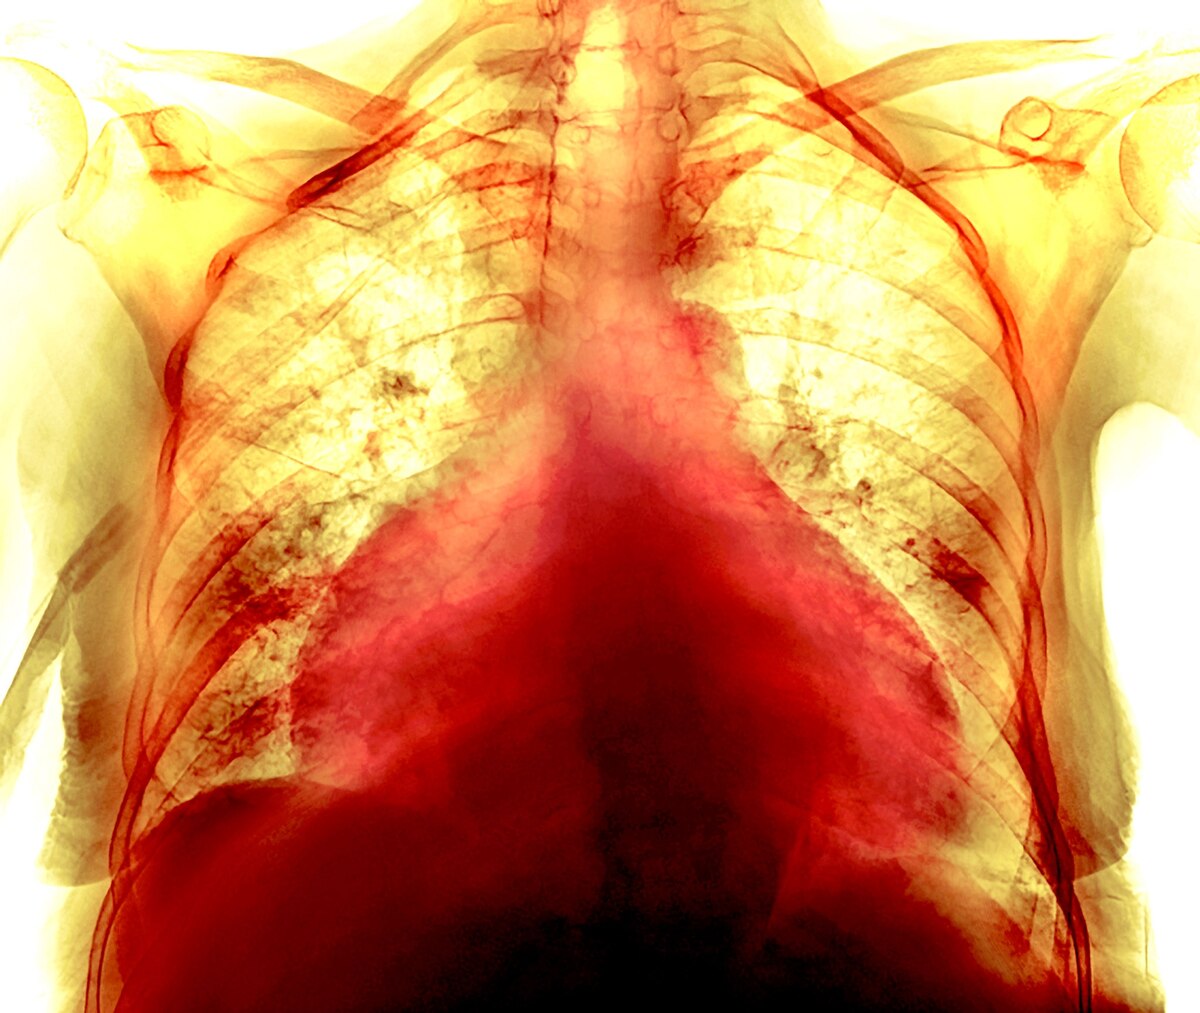

新型コロナは肺だけでなく、心臓や血管にも影響しているようだと、科学者たちはパンデミック(世界的大流行)の初期から考えていた。「非常に早い段階で、血液凝固が大きな役割を果たしていることに気づきました」と、米ニューヨーク大学ランゴーン医療センターの心血管疾患予防センターで所長を務めるジェフリー・バーガー氏は言う。

2020年3月の時点ですでに、血栓ができている患者が増え、心筋梗塞や脳卒中の増加につながっていた。また、解剖の結果、肝臓や腎臓など、通常はあまり血栓が発生しない場所に小さな血栓が見つかることが増えていた。

謎をさらに深めているのは、軽症や無症状だった人の中にも、動悸や胸の痛み、息切れ、極度の疲労感などの症状が長く続く人がいることだ。何が原因なのかはまだ科学者たちにもわかっていない。

新型コロナウイルスが心血管系を「二重」攻撃